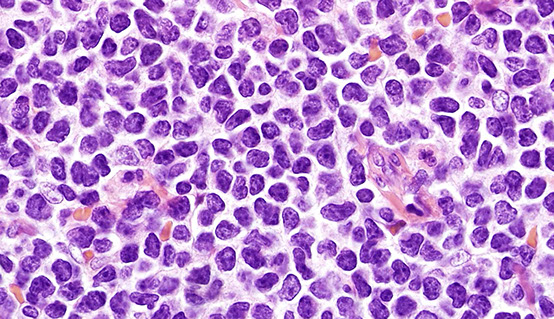

Thioflavin S (fluorescent scope needed)

IHC for Ig light chains, P component (found in most forms of amyloid), Amyloid A

Has become more and more routine to analyze amyloid with mass spec

- becoming the gold standard for amyloid typing

- IHC classification has well-known errors